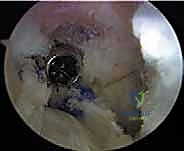

- الجراحة المجهرية وتنظير المفاصل بدقة 4K: يستخدم الدكتور هطيف أحدث تقنيات مناظير الركبة (Arthroscopy) المزودة بكاميرات عالية الدقة 4K، مما يتيح له رؤية أدق التفاصيل داخل المفصل، وتشخيص الأضرار المجهرية، وإجراء الجراحة بأقل تدخل جراحي ممكن (Minimally Invasive).

* التصوير بالرنين المغناطيسي (MRI): يوفر صورة مفصلة للأنسجة الرخوة. يحدد حالة الطعم المزروع سابقاً (هل هو ممزق، متآكل، أم سليم ولكنه غير فعال؟)، ويقيم حالة الغضاريف الهلالية والمفصلية.

* الأشعة المقطعية (CT Scan): في حالات الفشل الجراحي، تعتبر الأشعة المقطعية السلاح الأهم. فهي توفر نمذجة ثلاثية الأبعاد (3D) دقيقة جداً لمواقع الأنفاق العظمية القديمة وحجمها، مما يساعد الدكتور هطيف في اتخاذ قرار حاسم: هل يمكن حفر أنفاق جديدة فوراً، أم يجب إجراء الجراحة على مرحلتين؟